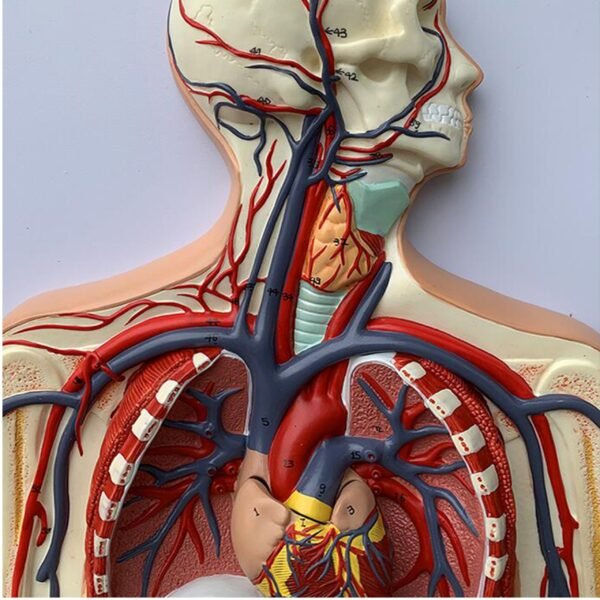

Blood Circulatory System model

* The model shows the main arteries and veins of the systemic blood circulation, with a total of 81 indications.